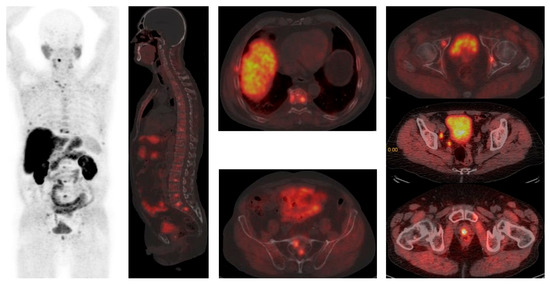

2.4. PSMA-Targeting Radiopharmaceutical PET/CT

4.3. Imaging in Metastatic Castration-Resistant Prostate Cancer (mCRPC)